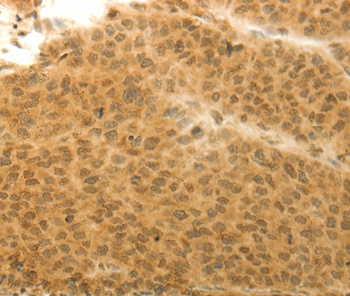

Immunohistochemical analysis of paraffin-embedded Human liver cancer tissue using #36924 at dilution 1/20.

Immunohistochemical analysis of paraffin-embedded Human colon cancer tissue using #36924 at dilution 1/20.